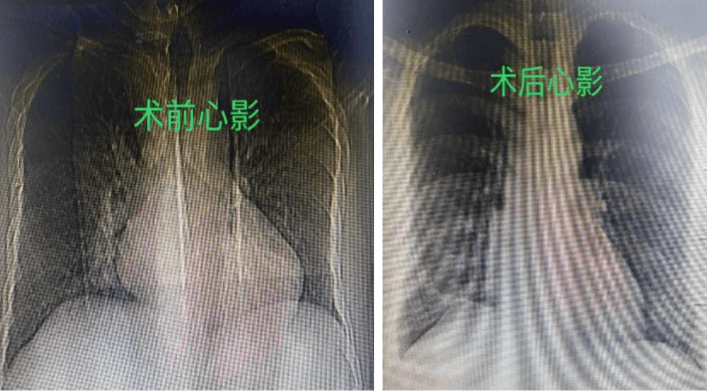

7月25日,在麻醉團(tuán)隊(duì)、體外循環(huán)等團(tuán)隊(duì)的保駕護(hù)航下,祝恒山主任帶領(lǐng)的手術(shù)團(tuán)隊(duì)在張先生的右側(cè)腋下切口了一個(gè)不到5厘米的小切口,開始為患者實(shí)施二尖瓣成形術(shù)和房間隔缺損修補(bǔ)術(shù),不到3個(gè)小時(shí),手術(shù)團(tuán)隊(duì)便順利地為患者的心臟進(jìn)行了“修補(bǔ)”,術(shù)后復(fù)查胸片及心臟超聲效果滿意。